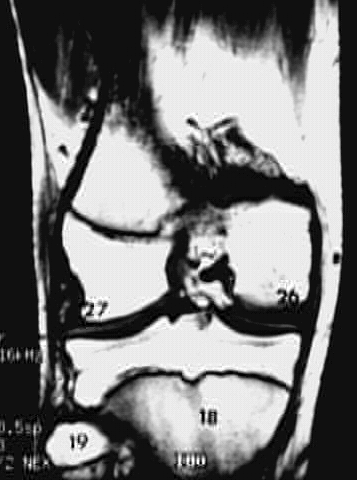

Lower Limbs: Knee MRI Zoom